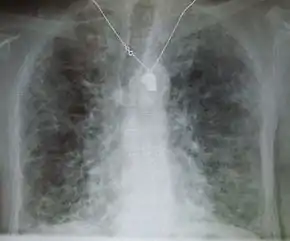

Lung

Side effects of oral amiodarone at doses of 400 mg or higher include various pulmonary effects.[27] The most serious reaction is interstitial lung disease. Risk factors include high cumulative dose, more than 400 milligrams per day, duration over two months, increased age, and preexisting pulmonary disease. Some individuals were noted to develop pulmonary fibrosis after a week of treatment, while others did not develop it after years of continuous use.[27] Common practice is to avoid the agent if possible in individuals with decreased lung function.

The most specific test of pulmonary toxicity due to amiodarone is a dramatically decreased DLCO noted on pulmonary function testing.